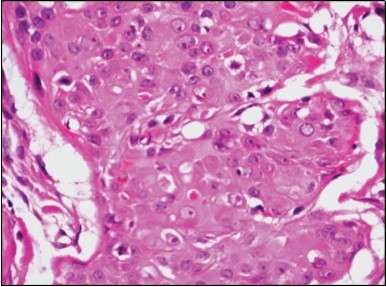

Granular arrangement of malignant cells and intercellular bridges are conspicuous with the demonstration of nuclear atypia, pleomorphism, prominent mitosis and tumour necrosis. A peripheral palisade is discernible within the cellular aggregates. Mitotic figures are common and can be quantified as up to 12 mitosis/ high power field. Tumour differentiation can prominently be of the ductal category with the demonstration of intra-cytoplasmic lumina. Comedo type tumour necrosis is evident along with foci of squamous differentiation The neoplasm is reactive to periodic acid Schiff ‘s (PAS) stain. (Figure 1, Figure 2, Figure 3, Figure 4, Figure 5, Figure 6, Figure 7, Figure 8, Figure 9, Figure 10, Figure 11, Figure 12, Figure 13.

Figure 4.Cellular atypia, mitosis and focal necrosis in eccrine porocarcinoma(16).

Figure 7.Aberrant and malignant epithelium with cellular proliferation and pleomorphism in eccrine porocarcinoma with frequent mitosis(19).

Figure 8.Disseminated atypical epithelial cells with cellular and nuclear pleomorphism, hyperchromasia, indistinct cytoplasm, vesicular nucleoli and central keratinization in eccrine porocarcinoma(20).